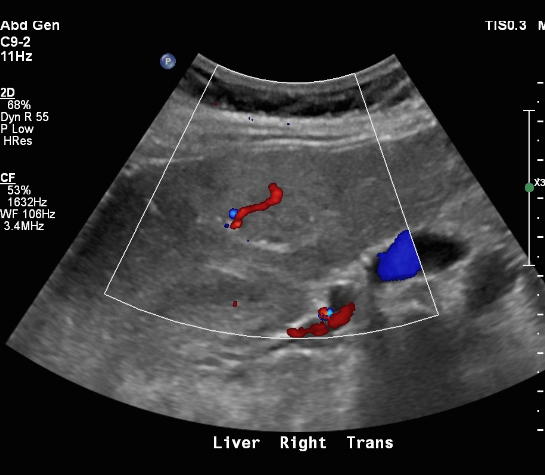

FNH (Focal Nodular hyperplasia) US finding

- hypoechoic lesion with central scar

- fatty liver